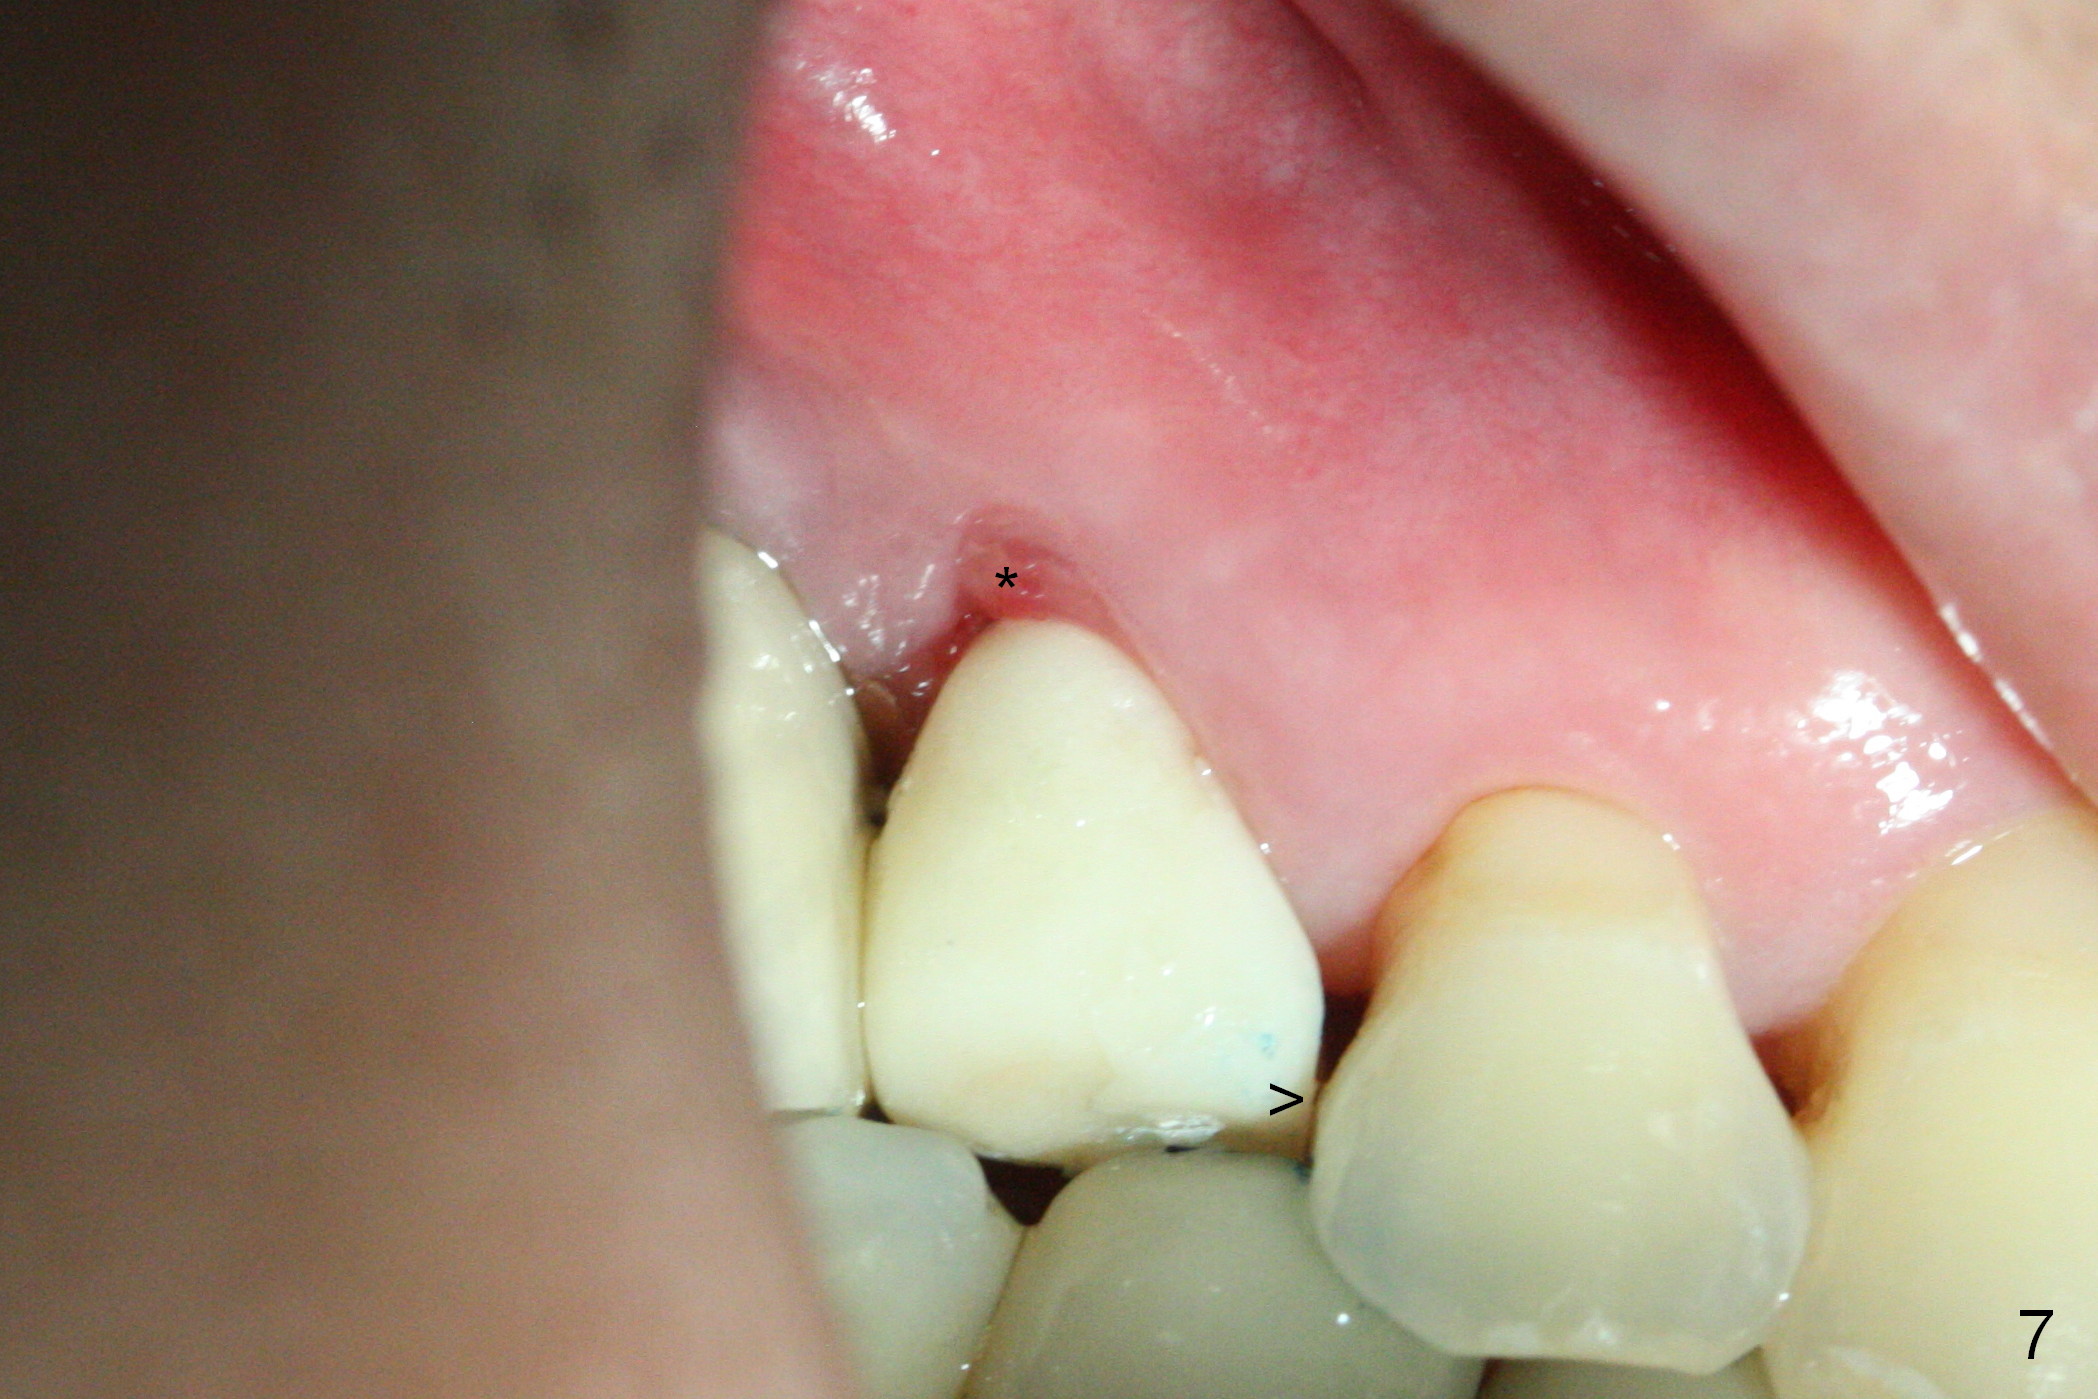

These are done 3 weeks postop (Fig.7) with granulation tissue having formed (*). The teeth #14 and 18 become symptomatic 4 weeks postop.